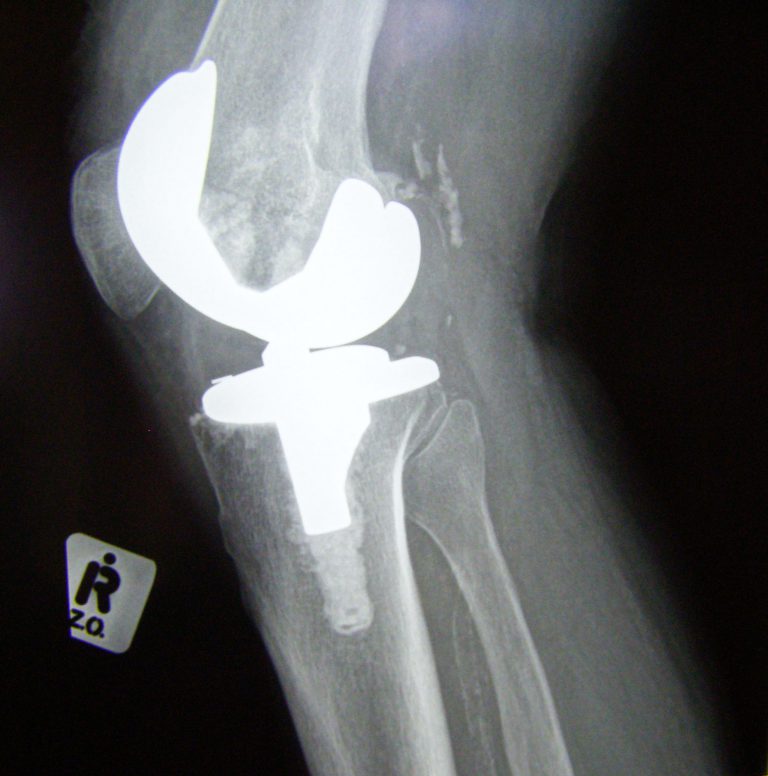

Joint Replacement, Past, Present and Future